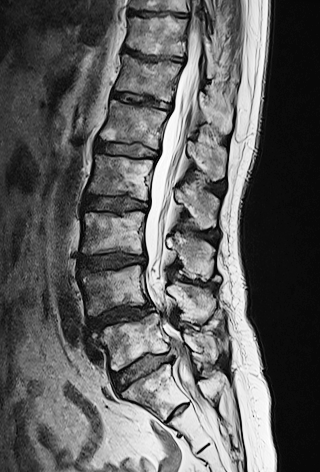

L4/L5レベル 腰椎すべり症

L5/S1レベル 椎間板ヘルニア・右背側に突出

整形外科病院MRI再検査にてヘルニア消失との見解。